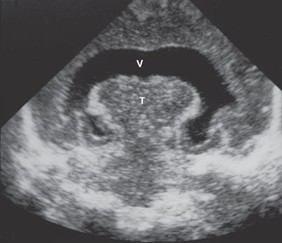

1. Holoprosencephaly (arhinencephaly; occurs when the prosencephalon fails to cleave down the midline such that the telencephalon contains a single ventricle. It is characterized by the absence of olfactory bulbs and tracts (arhinencephaly) and is often seen in trisomy 13 (Patau syndrome), trisomy 18 (Edward syndrome), short-arm deletion of chromosome 18, and Meckel syndrome. Because the fetal face develops at the same time as the brain, facial anomalies (e.g., cyclopia, cleft lip, cleft palate) are commonly seen with holoprosencephaly. Holoprosencephaly is the most severe manifestation of fetal alcohol syndrome resulting from alcohol use during pregnancy (especially in the first 4 weeks of pregnancy). The sonogram below shows a single, horseshoe-shaped ventricle (V) and fused thalami (T) typical of holoprosencephaly.

Holoprosencephaly (arhinencephaly).